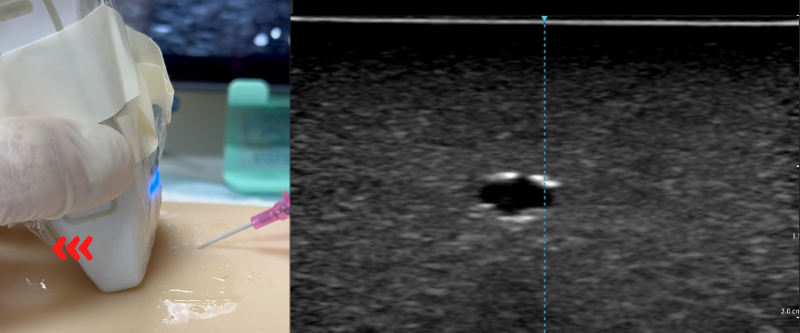

- Locate the needle tip: Insert the needle until the needle tip appears as a bright dot above the target vessel.

- Park the needle: Stop advancing the needle immediately. If the needle tip appears off from the midline, adjust the advancing direction.

- Insert the needle and locate the tip